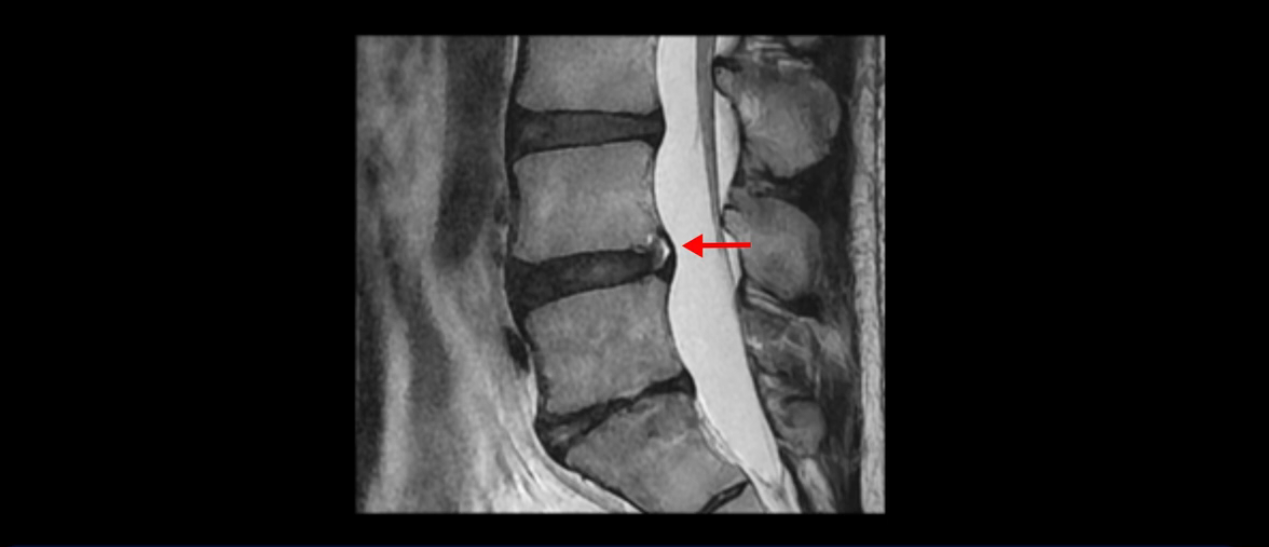

5번 1번 역시 가운데로 디스크 조금 밀려 나와있지만 신경 공간 넓이는 아주 넓어서 신경 눌림 있을 거라고 예상이 안됩니다.

앞서 1번 2번, 4번 5번, 5번 1번의 디스크가 찢어지고 조금 밀려 나온 게 최근에 찢어진 게 아니고 오래된 걸로 보인다고 말씀 드렸죠. 왜 그럴까요? 만약 급성으로 찢어진 것이라면 아주 심한 디스크성 통증이 있겠죠. 기침이나 재채기를 하면 심하게 아프고 허리를 조금만 구부리거나 비틀면 아주 날카로운 통증들이 생길 겁니다. 그런데 이분은 이런 증상이 전혀 아닙니다. 또 디스크의 밀려나온 정도도 전혀 심하지 않기 때문에 이분이 가지고 계신 양쪽 다리 저림, 특히 이분은 누워있을 때도 양쪽 발이 발가락까지 쑤신다고 하는데 이정도 디스크 때문에 그런 증상은 생길 수가 없는 겁니다. 이처럼 이분의 가벼운 디스크 탈출은 이미 오래 전에 진행되었고 섬유륜 자체는 이미 아문 상태인데도 디스크내장증을 진단받은 환자들 중에는 본인이 섬유륜 파열 환자라고 끝까지 믿는 분들이 많습니다. 다시 말하지만 디스크내장증이라는 진단을 받은 환자들을 보면 거의 전부 다 섬유륜 파열 증상이 아닙니다. 증상이 완전히 다릅니다. 진단이 애초에 잘못되면 어떤 치료를 받아도 좋아질 수 없습니다.

이 HIZ는 섬유륜이 찢어졌다가 이미 아문 뒤에도 얼마든지 보일 수 있는 흔적일 가능성이 있어서 재채기를 하면 아픈지, 허리를 구부릴 때 날카로운 통증이 생기는가 등의 증상으로 구별해야 하는데 MRI만 보고 HIZ가 보이면 그게 마치 통증의 원인인 것처럼 얘기하는 의사들이 있습니다. 이분 MRI를 자세히 보고 증상을 정말 자세히 들어본 의사가 있었더라면 다른 환자분들처럼 증상과 MRI가 일치하지 않는다는 얘기를 들을 수 있었을 텐데 이분은 그런 얘기는 듣지 못했습니다.